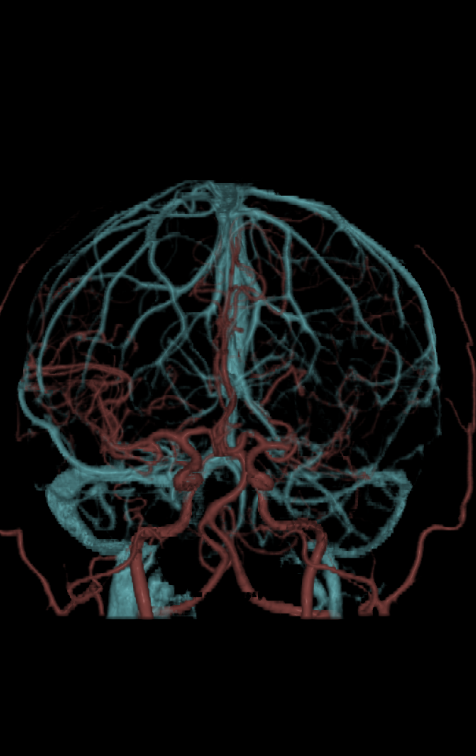

4D一站式卒中检查

天河640可实现单圈扫描的全脑覆盖成像。采用宽体采集进行头部平扫、动态CTA及CTP成像,一次检查即可获得全脑平扫图像、动静脉造影图像和灌注图像。结合集成脑灌注分析、4D动静脉动态评估等高级后处理手段,不仅可应用于急诊缺血性脑卒中的影像评估,还可助力脑血管畸形、脑动脉瘤等其他脑血管病的结构和功能评估。

图片说明:颅脑血管成像及脑卒中灌注成像